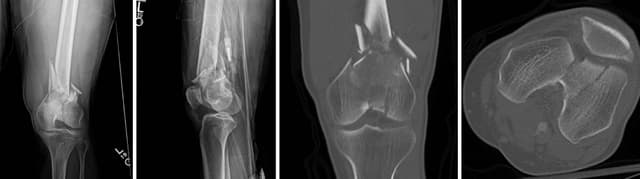

Imaging

Pre-op